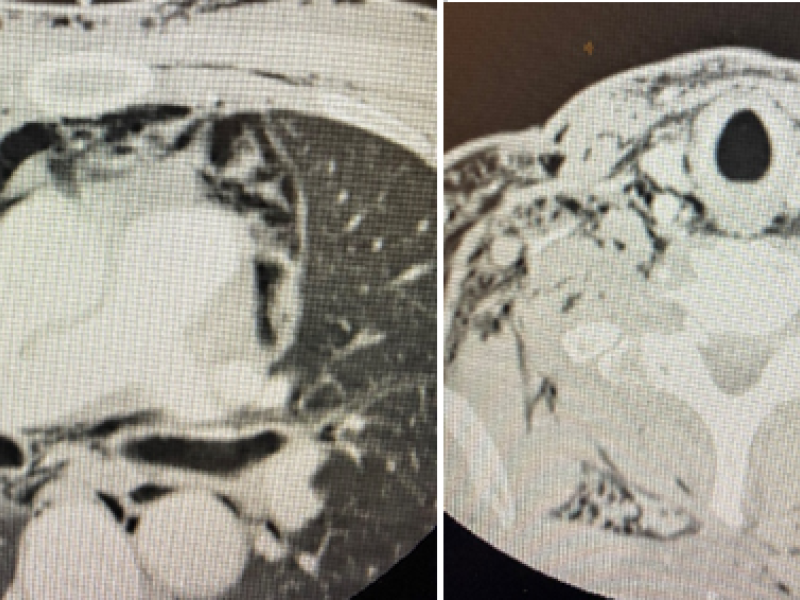

A 51 yo M presents to the ED with 2 self inflicted stab